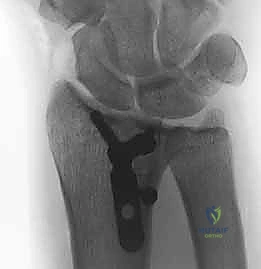

- الأشعة السينية (X-rays):

هي الخطوة الأولى لتقييم الكسر. يتم أخذ صور من زوايا متعددة (أمامية خلفية، جانبية، ومائلة) لتحديد موقع الكسر الأساسي ودرجة الانزياح والتقصير في عظم الكعبرة.

- التصوير المقطعي المحوسب (CT Scan) مع إعادة البناء ثلاثي الأبعاد:

هذا هو المعيار الذهبي الذي يعتمده الدكتور هطيف لجميع كسور المفصل المعقدة. تتيح الأشعة المقطعية رؤية كل شظية عظمية بوضوح تام، وتحديد حجمها، وموقعها، ودرجة تفتت السطح المفصلي بدقة ملليمترية. من خلال إعادة البناء ثلاثي الأبعاد (3D Reconstruction)، يمكن للدكتور هطيف "رؤية" الكسر من جميع الزوايا قبل فتح الجلد، مما يسمح له باختيار الغرسات (الصفائح والمسامير) الدقيقة لكل شظية وتحديد المداخل الجراحية المثلى.